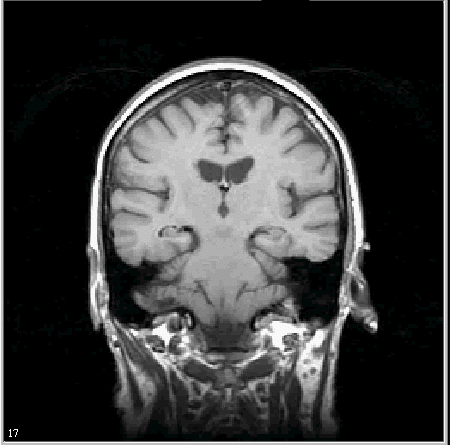

MIPAV provides tools that allow researchers to automatically, semi-automatically, and manually identify and modify volumes of interest (VOIs). Nodes on the VOI can be moved or deleted, and new points can be added. VOI types include point, 2D line, 2D rectangle, 3D rectangle, 2D ellipse, 2D polygon, 3D polygon, and interactive level-set.